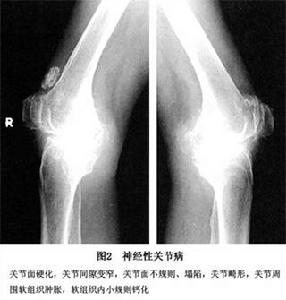

2.CT檢查 CT具有解析度高的優點,能更好地顯示病灶的結構、骨質破壞和鄰近軟組織的情況。儘管X線是本病診斷的首選方法但CT與X線結合更能清楚顯示病變有助於確定關節腔積液的具體範圍和積液量,區分關節積液和軟組織腫脹引起的軟組織密度增高,區分游離骨塊是在關節腔還是關節周圍軟組織內。對於平片不能診斷或難以確定病變範圍的病例,CT可作為重要的檢查手段加以利用(圖2)。